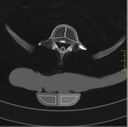

Dieses weltweit einmalige Phantom bietet erstklassige Übungsmöglichkeiten für die Lagerungs- und Einstelltechnik in der Projektions-Radiographie und gehört eigentlich zur Grundausstattung jeder Röntgen-Ausbildungsstätte. Das Phantom enthält ein natürliches menschliches Skelett sowie die Umrisse von Kehlkopf, Lunge, Herz und Nieren (Organe erscheinen als Schatten auf den Röntgenbildern), dadurch können mit dem Phantom echte Röntgenaufnahmen wie beim Patienten gemacht werden. Durch die Verwendung des echten Skeletts können Leitstrukturen im Knochen erkannt werden, was bei Kunststoffskeletten nicht möglich ist. Bei der Montage des Phantoms wird besonderer Wert auf die Darstellung der Gelenkspalte gelegt. Die Gelenke sind voll beweglich montiert, und ermöglichen die Lagerung in den normalen Röntgenpositionen (z.B. Froschposition, Pro- und Supination des Unterarms). Die Arme können nach oben bewegt werden, so dass das Modell auch für alle knöchernen Untersuchungen im CT verwendet werden kann. Bei jedem Phantom handelt es sich um ein handgefertigtes Unikat, welches sich in Größe und Ausführung unterscheiden kann. Je nach Modell können pathologische Befunde vorhanden sein, die äußere Erscheinung kann sich je nach Größe des Modells unterscheiden. Die neue Ausführung dieses Modells wurde in Zusammenarbeit mit einer namhaften deutschen Schule für Med. Techn. Radiologieassistenten komplett überarbeitet und erfüllt alle Anforderungen für die Ausbildung. Der Verkauf dieses Phantoms erfolgt nur gegen Nachweis der medizinischen Verwendung. Natürliche Größe.